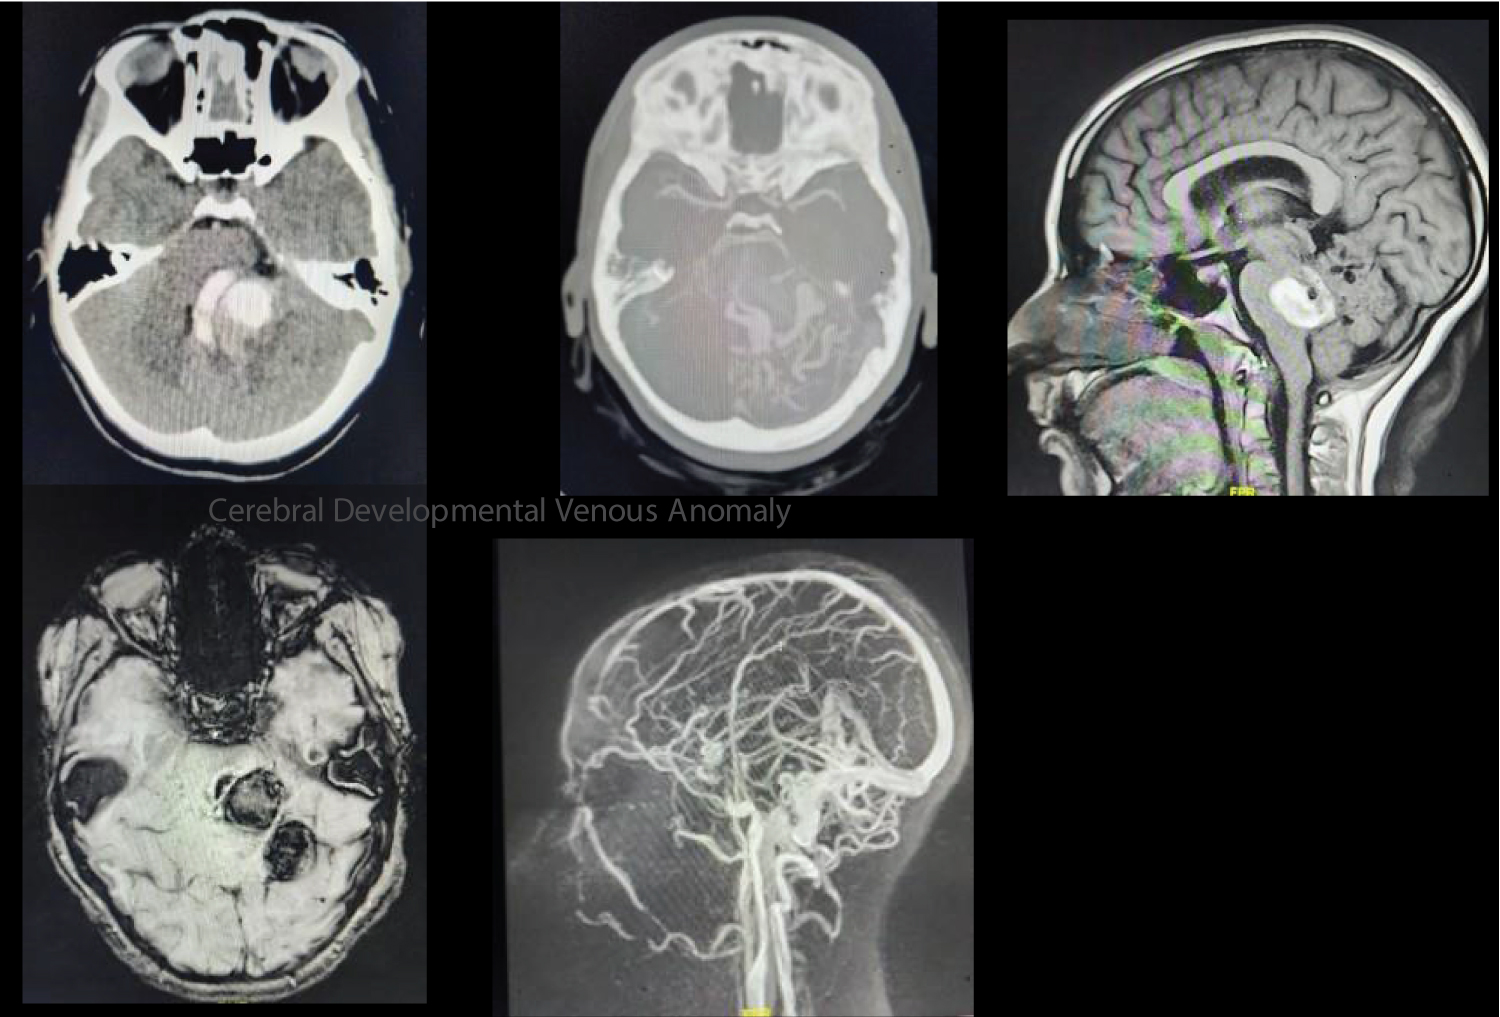

Imaging investigations done included CT, CT angiography, MRI, and MRV scans showing multiple variable left cerebellar DVA with anomalous posterior fossa cerebellar draining veins, slightly engorged without thrombosis or stenosis (Figure 1).

Figure 1: Multiple variables left cerebellar DVA with anomalous posterior fossa cerebellar draining veins. View Figure 1